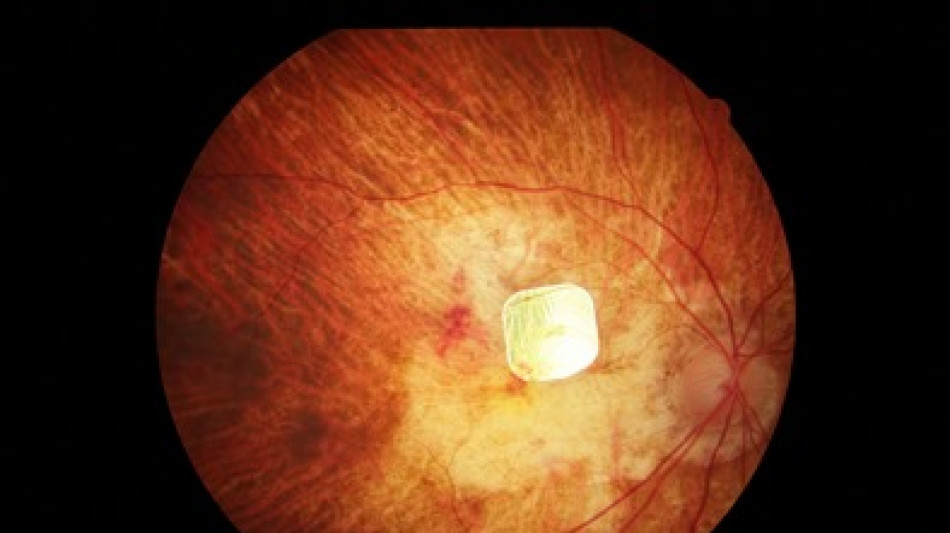

Buoni risultati a un anno dall'impianto di microchip retinici in 38 pazienti legalmente non vedenti: l'impianto ha ripristinato la visione in questi pazienti, consentendo loro di leggere sequenze di lettere con un miglioramento clinicamente significativo dell'acuità visiva misurabile mediamente in 4-5 righe del tabellone che usa l'oculista e nei casi migliori 11-12 righe. Si tratta dei risultati preliminari dello studio clinico PRIMAvera, su pazienti con atrofia geografica (l'esito più grave della degenerazione maculare senile che porta al deterioramento della vista), ai quali è stato impiantato il sistema retinico PRIMA. Anticipati dall'azienda Science Corporation, i risultati preliminari sono stati presentati in Spagna al Congresso mondiale dedicato alla visione artificiale e alle interfacce cervello-computer 'Brain & Chip '24', da Andrea Cusumano dell'Università di Tor Vergata, Direttore Scientifico del progetto in Italia, in presenza tra gli altri anche di Daniel Adams, direttore scientifico di Neuralink. I pazienti che hanno partecipato alla sperimentazione erano incapaci di leggere e di riconoscere i volti. Ora la loro acuità visiva è migliorata e alcuni sono in grado di leggere testi più lunghi. "I risultati rappresentano una pietra miliare nel trattamento della cecità come esito della degenerazione maculare senile" - afferma Cusumano. La degenerazione maculare legata all'età, ricorda Cusumano, colpisce in Italia almeno un milione di persone e rappresenta la prima causa di cecità legale e ipovisione nel mondo occidentale. Il microchip impiantato (PRIMA) misura meno di un terzo di un capello, è wireless, funziona con l'ausilio di occhiali con una mini-fotocamera integrata per acquisire le immagini e un computer tascabile che le trasforma in un 'disegno' di luce. Il microchip traduce la luce in stimoli elettrici inviati alla corteccia visiva. L'uso di questa tecnologia in futuro potrebbe essere esteso anche ad altre malattie retiniche, come la retinite pigmentosa. "Potenzialmente in Italia ne potrebbero beneficiare circa 20 mila pazienti, 8 milioni nel mondo" - conclude Cusumano.